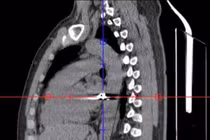

Việc cứu sống bệnh nhân trong trường hợp vết thương do đạn bắn xuyên ngực là một thành công đáng ghi nhận nhờ phản ứng nhanh trong cấp cứu.